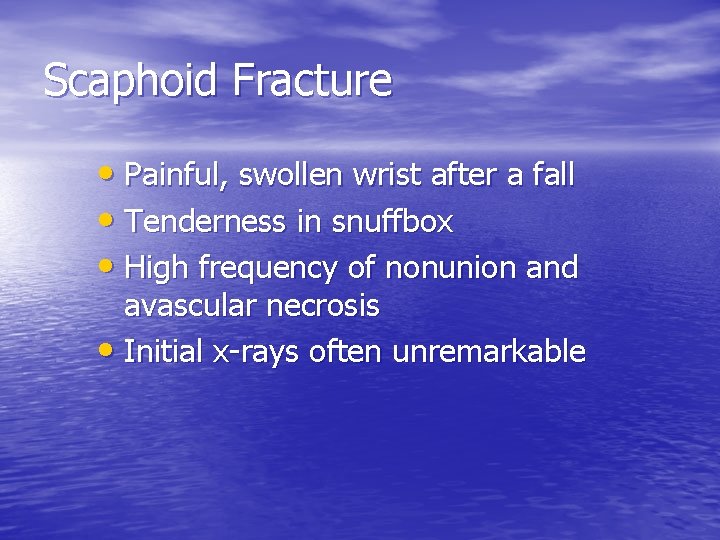

Scaphoid Fracture • Painful, swollen wrist after a fall • Tenderness in snuffbox • High frequency of nonunion and avascular necrosis • Initial x-rays often unremarkable